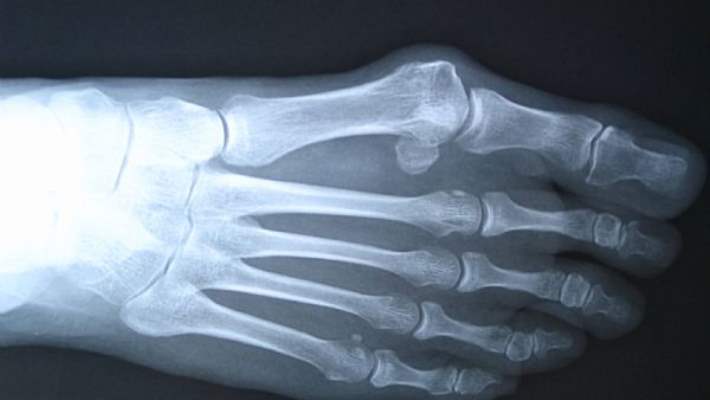

- Kemik: Kalsitonin, kemik matrisini “sindirip” kanda kalsiyum ve fosfor açığa çıkaran bir tür hücre olan osteoklastların etkilerini engelleyerek kemiğin emilimini bastırır.